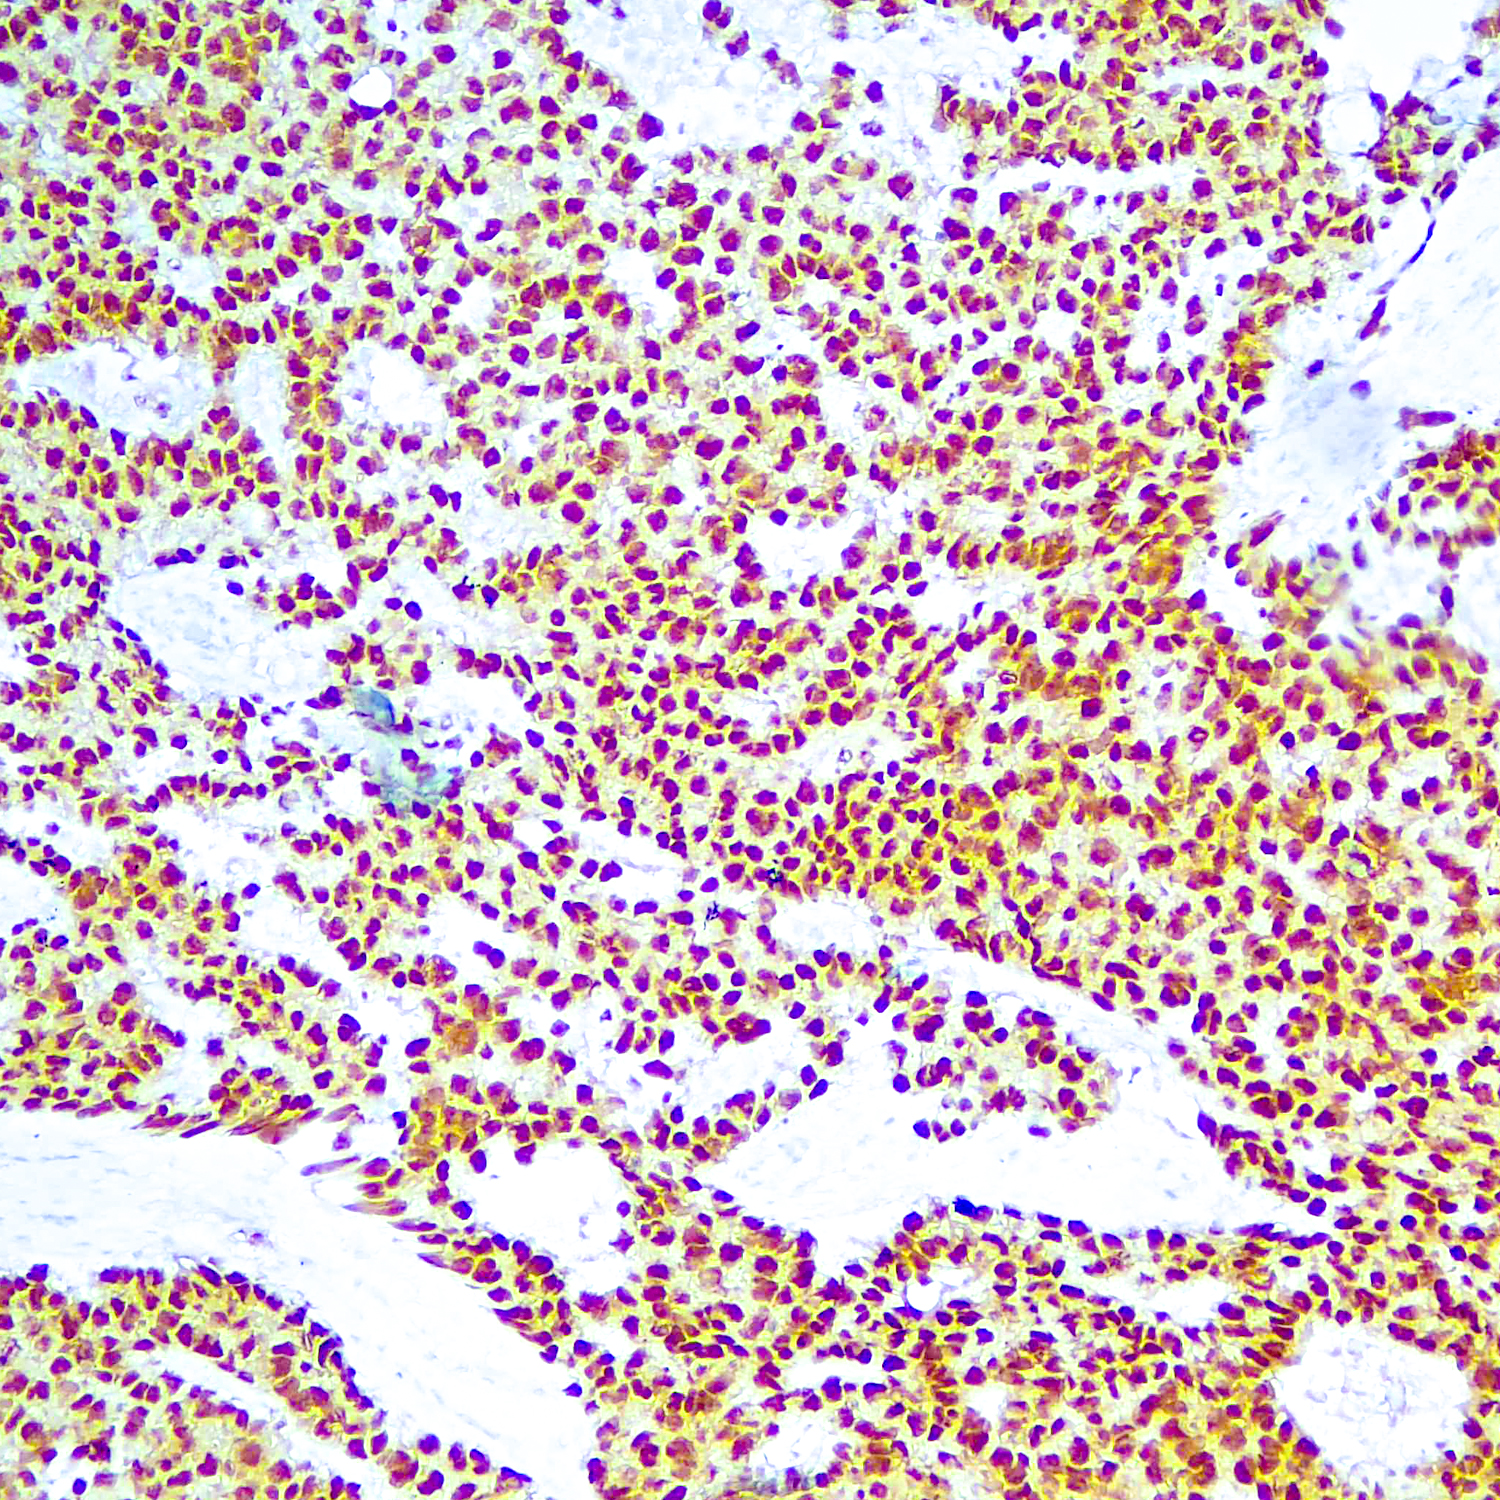

OCT-3/4 (also known as POU5F1) is a transcription factor that has been recognized as fundamental in the maintenance of pluripotency in embryonic stem cells and primordial germ cells. It has been proposed as a useful marker for germ cell tumors (GCT) that exhibit features of pluripotentiality (seminoma/dysgerminoma, germinoma and embryonal carcinoma. OCT-3/4 immunostaining has been shown to be sensitive and specific for GCT, whether in primary gonadal or extragonadal sites or in metastatic lesions.

| Positive Control Tissue | Seminoma |